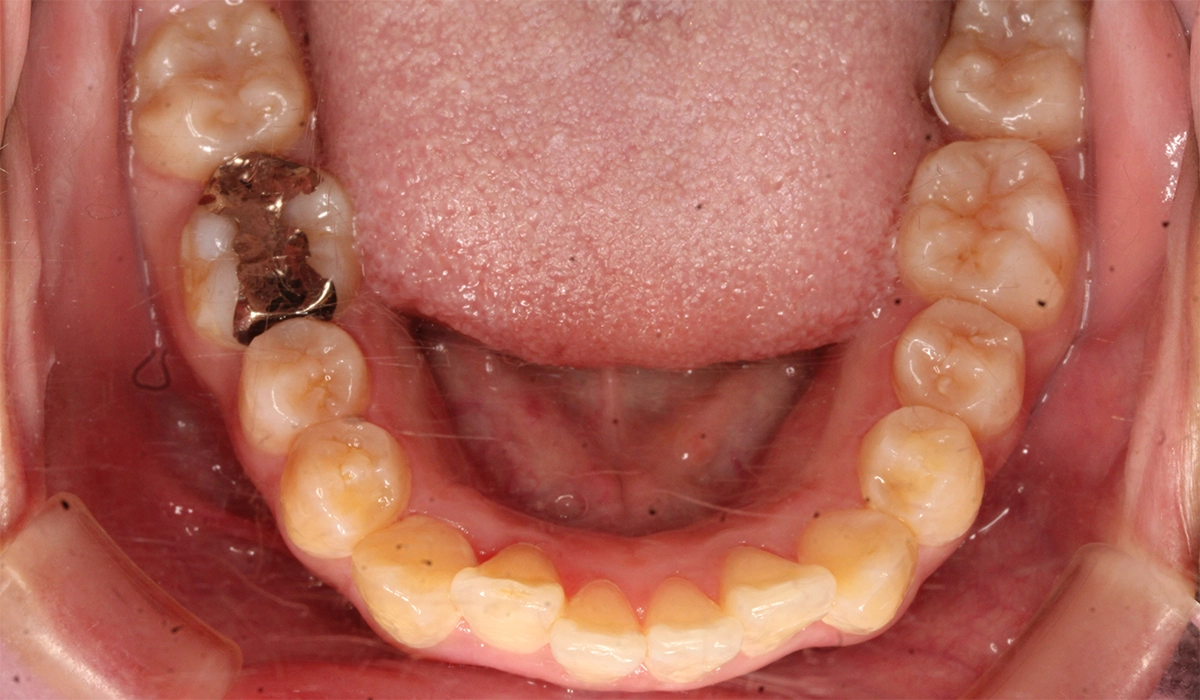

術後:下顎